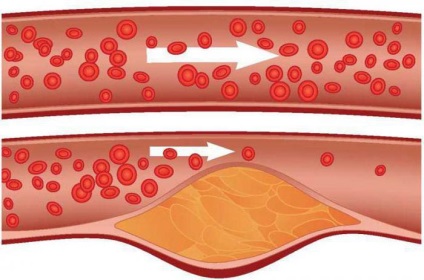

atherosclerosis az aorta

Atherosclerosis az aorta és az ágai - amely egy olyan kórkép, amely jellemzi a növekedés plakkok a vaszkuláris lumen, amely ezt követően vezet a lumen szűkülése, és a vérrögök kialakulását.

Alapját képező patológia egyenlőtlenség aránya lipidfrakciók, felé a növekedés a koleszterin, amelyet letétbe plakkok az aorta és az aorta ágak.

Súlyosbító tényező a dohányzás, a cukorbetegség, az öröklődés, a testmozgás hiánya.

megnyilvánulásai atherosclerosis

Elég gyakran fordul elő érelmeszesedés semmilyen tünet, ami annak köszönhető, hogy a nagy méret az aorta (valamint osztályok, ágai az aorta), a fejlesztési és az izom elasztikus rostok. A növekedés a plakk vezet túlterhelése a szív, amely megnyilvánul a nyomás hullámok, fáradtság, szívdobogás.

A betegség progresszióját folyamat kiterjed az aortaív ágak fő- és visszirányú szakaszok, beleértve az artériák, hogy táplálja a szív. Ebben az esetben, azt tapasztalja a következő tünetek: angina pectoris (mellkasi fájdalom, hogy adják a lapocka vagy a kar, légszomj), emésztési zavarok és vesefunkció, vérnyomás ugrik, hideg végtagok, szédülés, fejfájás, gyakori ájulás, gyengeség a karok.